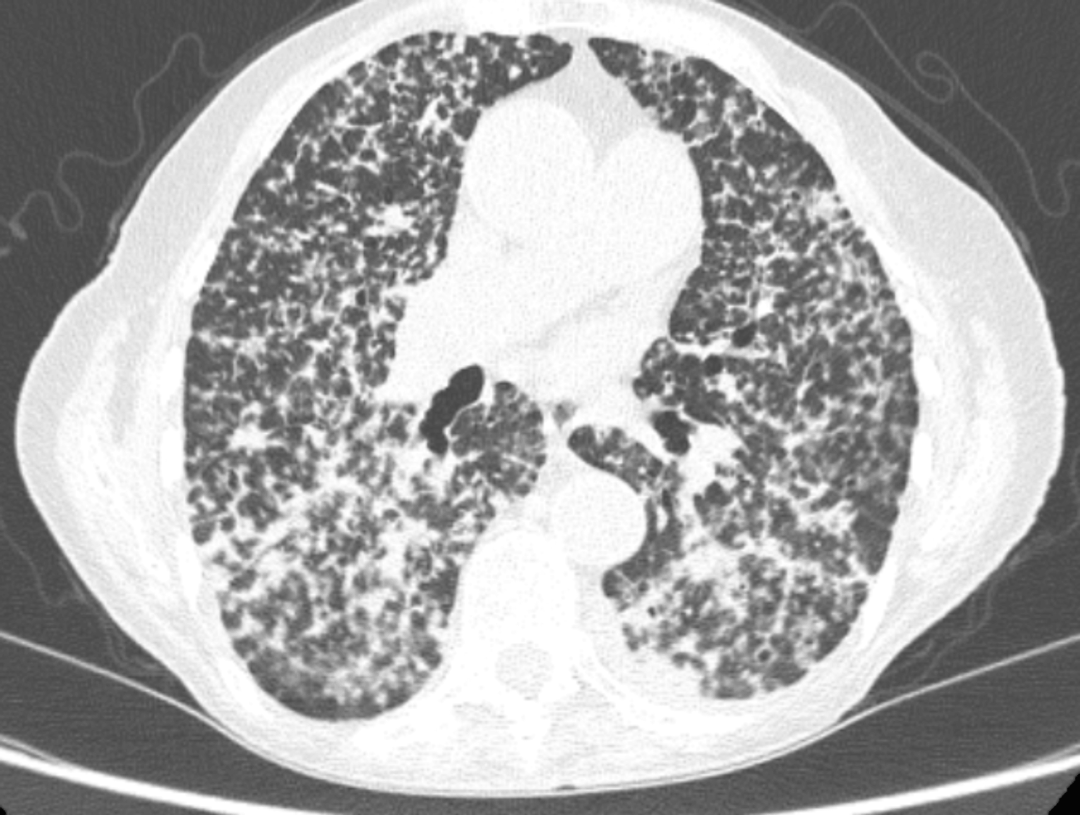

病史摘要:33 岁女性,无吸烟饮酒及特殊家族史,因“活动后胸闷、气短”于 2020 年 9 月 4 日就诊。胸部高分辨率 CT 提示左下叶基段肿块阴影伴左肺散在小结节。心包积液和胸腔积液涂片、支气管镜病理均证实为左下叶基底段腺癌,基因检测示 EGFR 外显子 19 突变和 TP53 突变,临床诊断左肺腺癌(T3N3M1a IVA 期,EGFR ex19del+,TP53+)。 诊疗过程:一